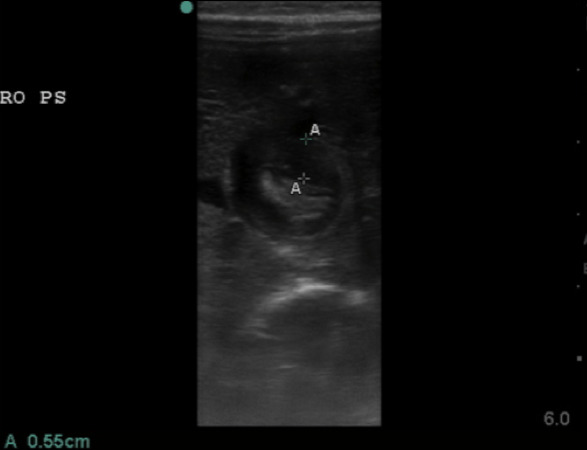

- Figure 7. Hypertrophied pyloric muscle in short axis measuring 5.5mm

- A thickness of ³3mm is considered abnormal or hypertrophied